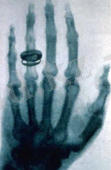

В. К. Рентген жұбайы Бертаның қолын 1895 ж. 22 желтоқсанында жаңа сәуле арқылы суретке түсіріп алады. 15 минуттық экспозициядан кейін алғашқы рентгенограмма пайда болады, онда анық білезік сүйектері мен екі сақина байқалады. Кейбір әдебиет деректері бойынша, өз саусақ сүйектерінің суретін көрген Берта есінен танып қалған көрінеді.

3-сурет. Саусақ сүйектері

Бертаның саусақ сүйектерінің рентгендік суреті - әлемдегі ең бірінші рентгенограмма болып саналады.